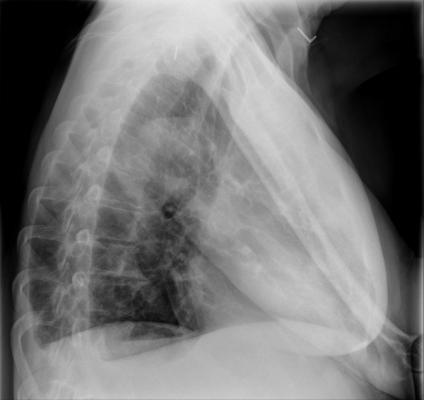

November 21, 2014 — In a breakthrough that could substantially improve physicians' ability to rapidly evaluate patients suspected to have Ebola, radiologists at Emory University Hospital have devised a protocol for obtaining chest radiographs using portable computed radiography. The protocol not only limits the exposure of personnel and equipment to body fluids, it also minimizes the risk of contaminants leaving the isolation unit by use of thorough decontamination procedures.

The step-by-step protocol is outlined in an article published ahead of print in the American Journal of Roentgenology.